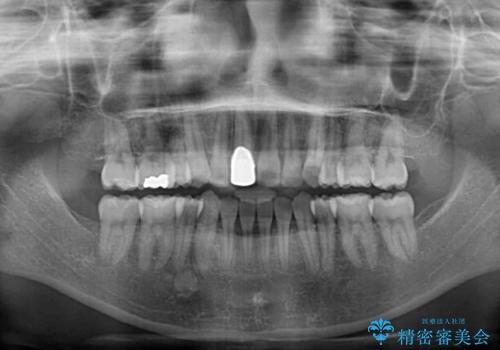

- 八重歯や前歯のデコボコを気にして来院された患者様です。

歯列が前方に傾斜しており、デコボコが強かったため、上下左右第一小臼歯4歯を抜去し、ワイヤー装置による矯正治療を行うこととしました。

上下の正中がずれていましたが、抜歯矯正であったので、極力正中位置を合わせるように治療を進めて行きました。

顎間ゴムの使用などにより、正中位置を改善することができました。